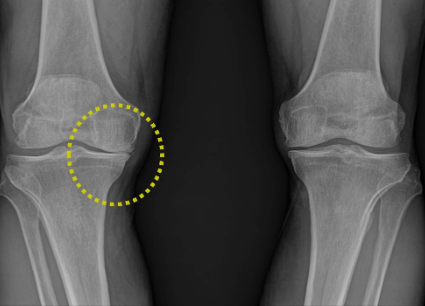

특히 저는 어릴때부터 무릎이 안좋았는데요,

중학교 때 관절염(정확히는 박리성 골연골염)으로 수술을 2번, 대학교와서 1번의 수술을 했었습니다.